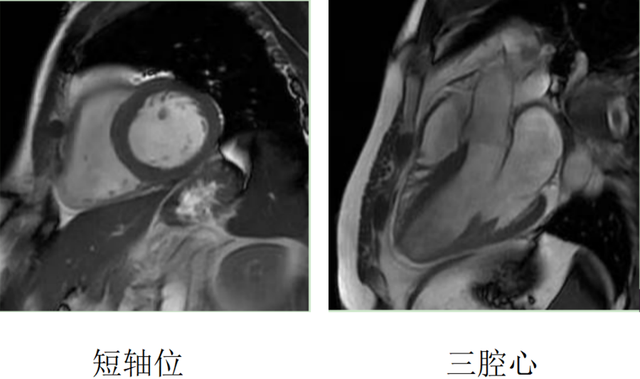

心脏磁共振被称为心脏“一站式”检查,通过多参数成像能够对心脏的结构、功能、室壁运动、心脏瓣膜、心肌灌注和活性进行“一站式”评估。主要通过电影序列(短轴、两腔心、四腔心、三腔心)、T2WI序列、首过灌注序列以及延迟强化序列对心脏进行综合成像。